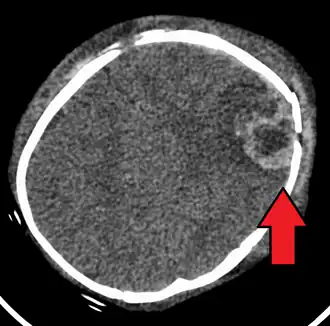

Vooral het hoofd van een baby is erg broos en kwetsbaar omdat het naar lichaamsverhouding erg groot is en de nekspieren van het jonge kind nog maar weinig zijn ontwikkeld. Wanneer de baby zodanig wordt geschud dat het hoofdje heen en weer beweegt, kan het schudden beschadigingen van hersenen, bloedvaten en zenuwen veroorzaken, met blijvend letsel of met de dood tot gevolg. De gevolgen van de beschadiging aan bloedvaten, de hersenen of hersenzenuwen bij het shakenbabysyndroom zijn blijvend. Ieder jong kind dat, heftig of niet, op deze wijze wordt geschud, gedurende vijf seconden of langer, heeft onmiddellijk medische hulp nodig. Snelle medische hulpverlening kan het verergeren van de gevolgen voorkomen, bijvoorbeeld door een hersenoedeem te behandelen.

Er zijn de volgende medische indicaties voor het shakenbabysyndroom:

- Hersenbloeding